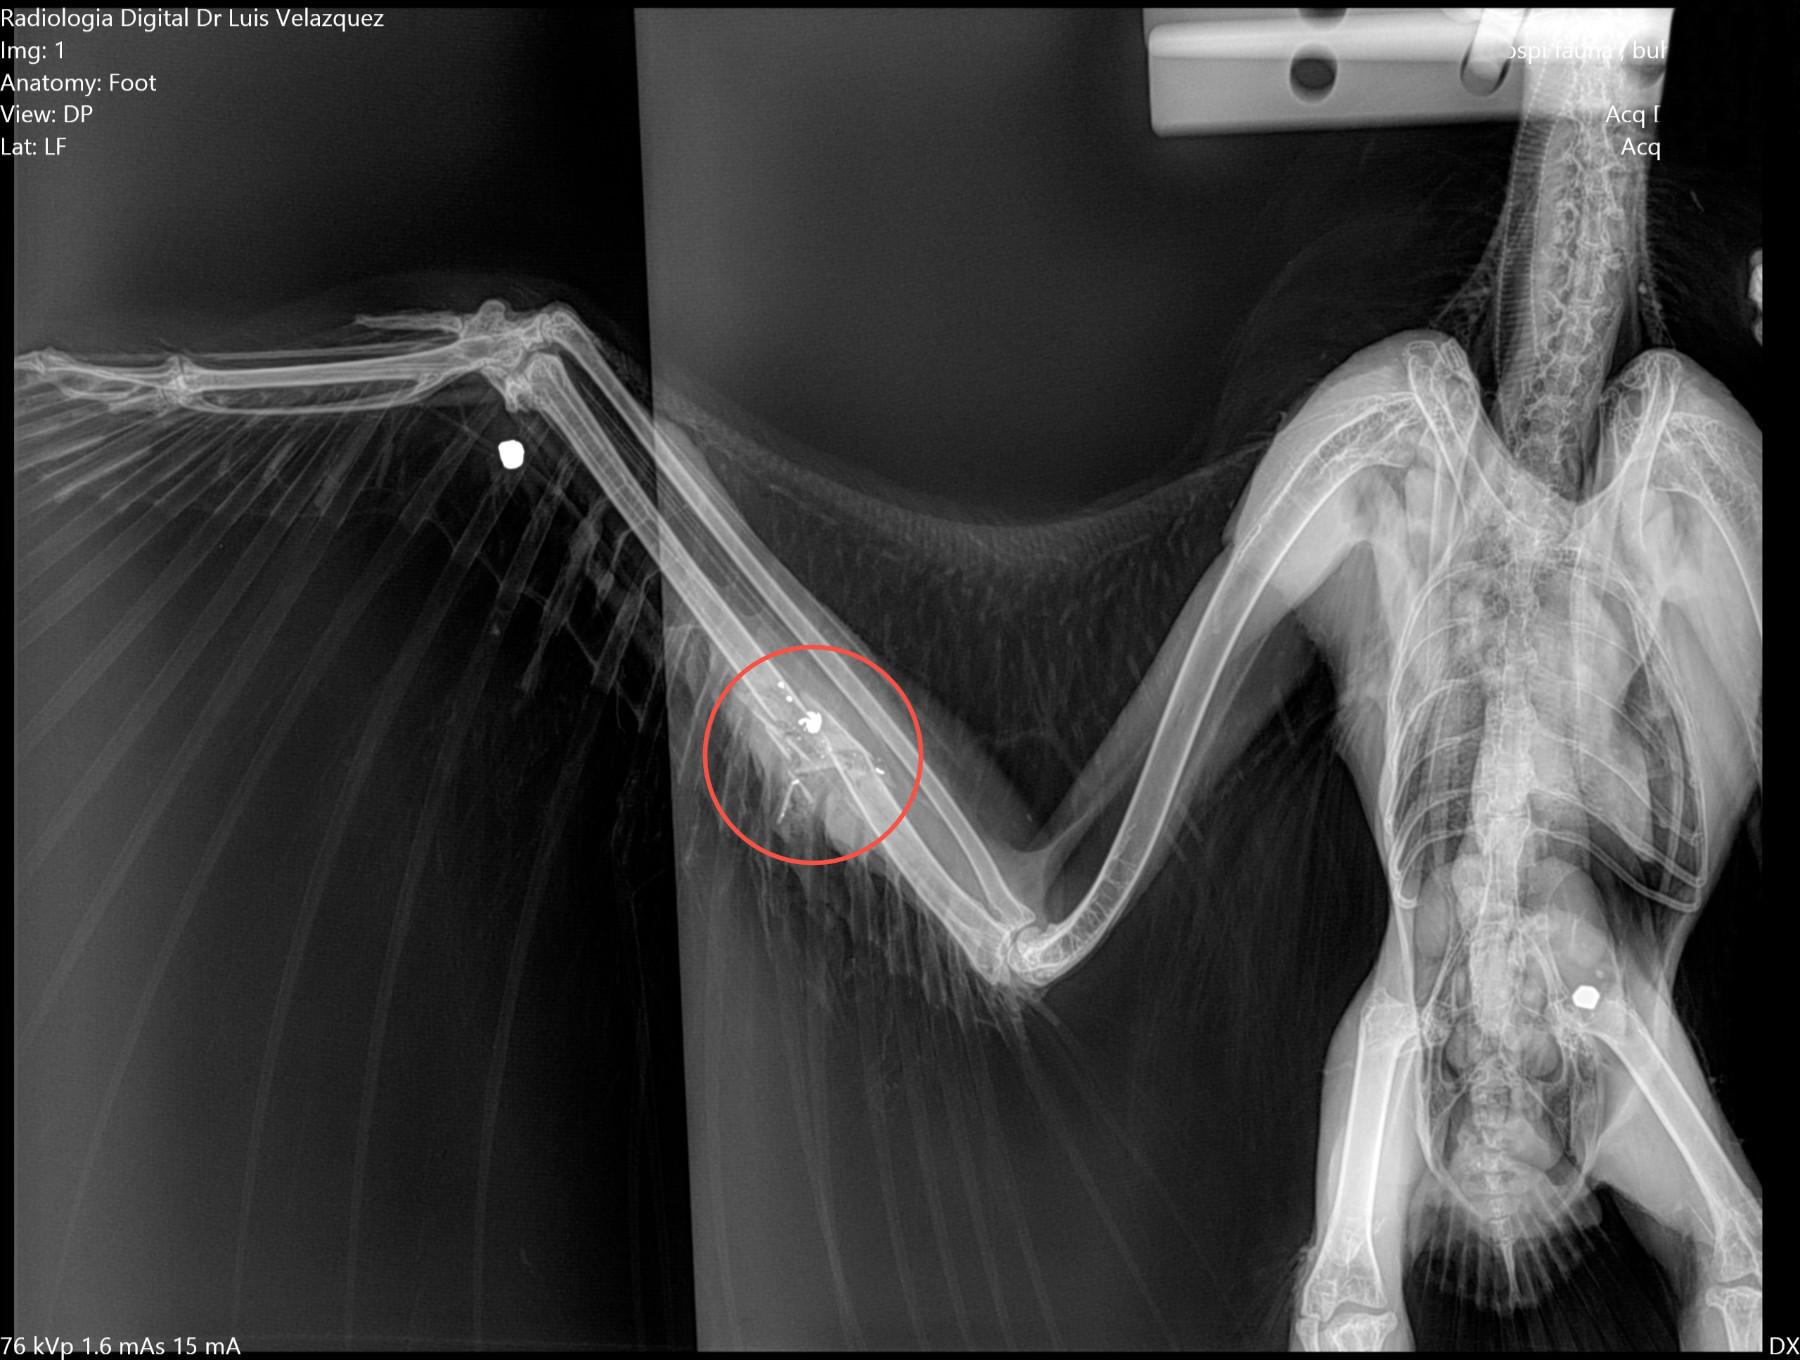

Cambios Térmicos en las Extremidades de Caballos,

Asociados a Golpes y su Evaluación por Termografía.

Los caballos de salto, en competencia, pueden derribar obstáculos y lastimarse. Si se golpean, no siempre claudican. Considerando al calor como un signo de inflamación, se evaluaron los cambios térmicos de 6 áreas de las extremidades torácicas y pelvianas de 23 caballos de salto en nivel de competencia de 1.05 a 1.60 m de altura, por medio de termografía durante 4 días de competencia (N=2208 áreas).